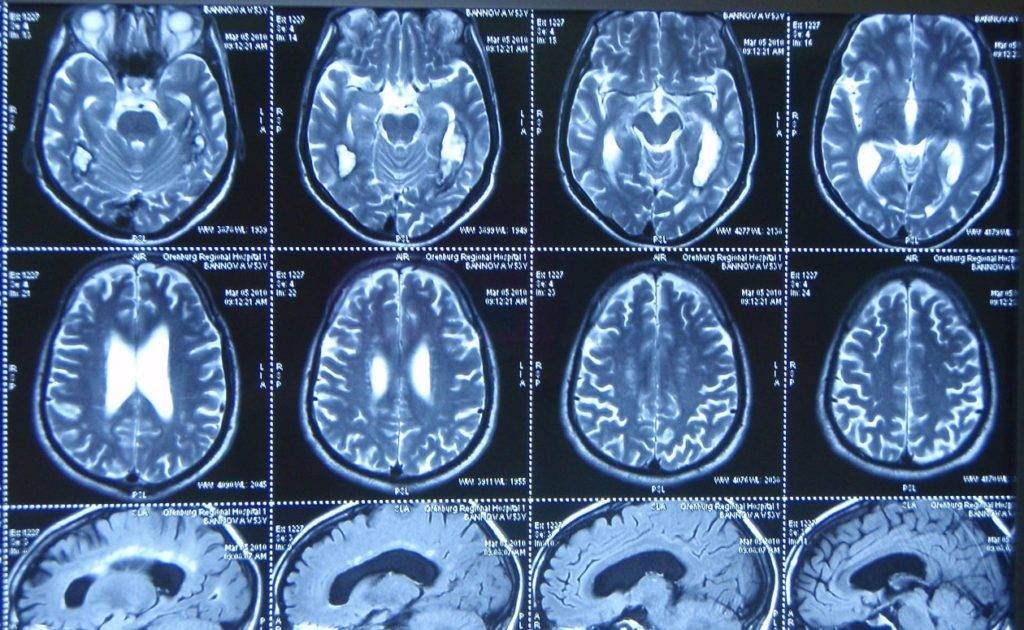

Возможности МРТ диагностики применяются в самых различных областях медицины. Однако наибольшее значение метод приобрел в неврологии, совершив революцию в диагностике патологий головного мозга. Благодаря МРТ исследованиям мы узнали много нового о том, как работает центральная нервная система.

МРТ головного мозга позволяет выявить очаги аномальной нервной ткани (опухоль, кровоизлияние, ишемия), аневризмы, признаки повышения внутричерепного давления, оценить состояние сосудов головы и шеи, лимфатических узлов и органов шеи.